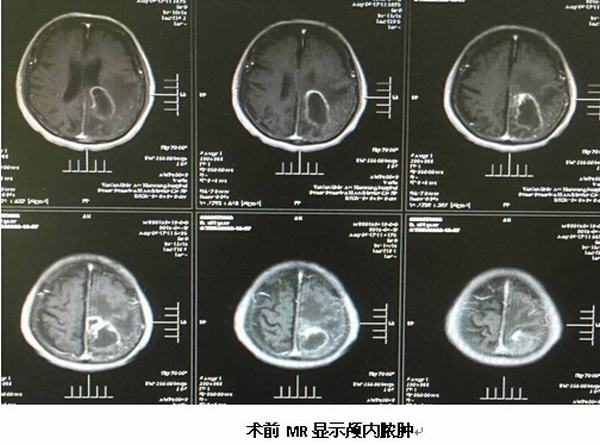

繼完成第一例腦立體定向手術后不久,于2016年4月25日我院神經(jīng)外科又完成一例89歲高齡腦膿腫患者的腦立體定向膿腫穿刺引流術,按照手術標準流程操作,術中清除膿液約30ml,經(jīng)置管持續(xù)引流并局部及全身注射抗菌素治療,目前患者頭顱CT顯示膿腔已消失,體溫正常,神志清楚,各項生命體征平穩(wěn)。